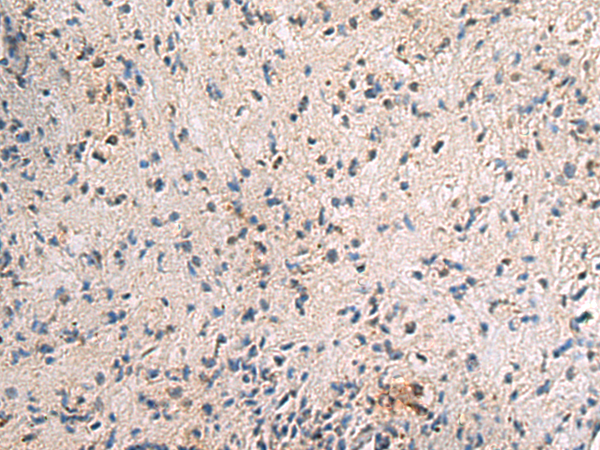

分类: 科研抗体货号: P03427别名: S31mt; IMOGN38; MRP-S31应用: IHC反应种属: Human